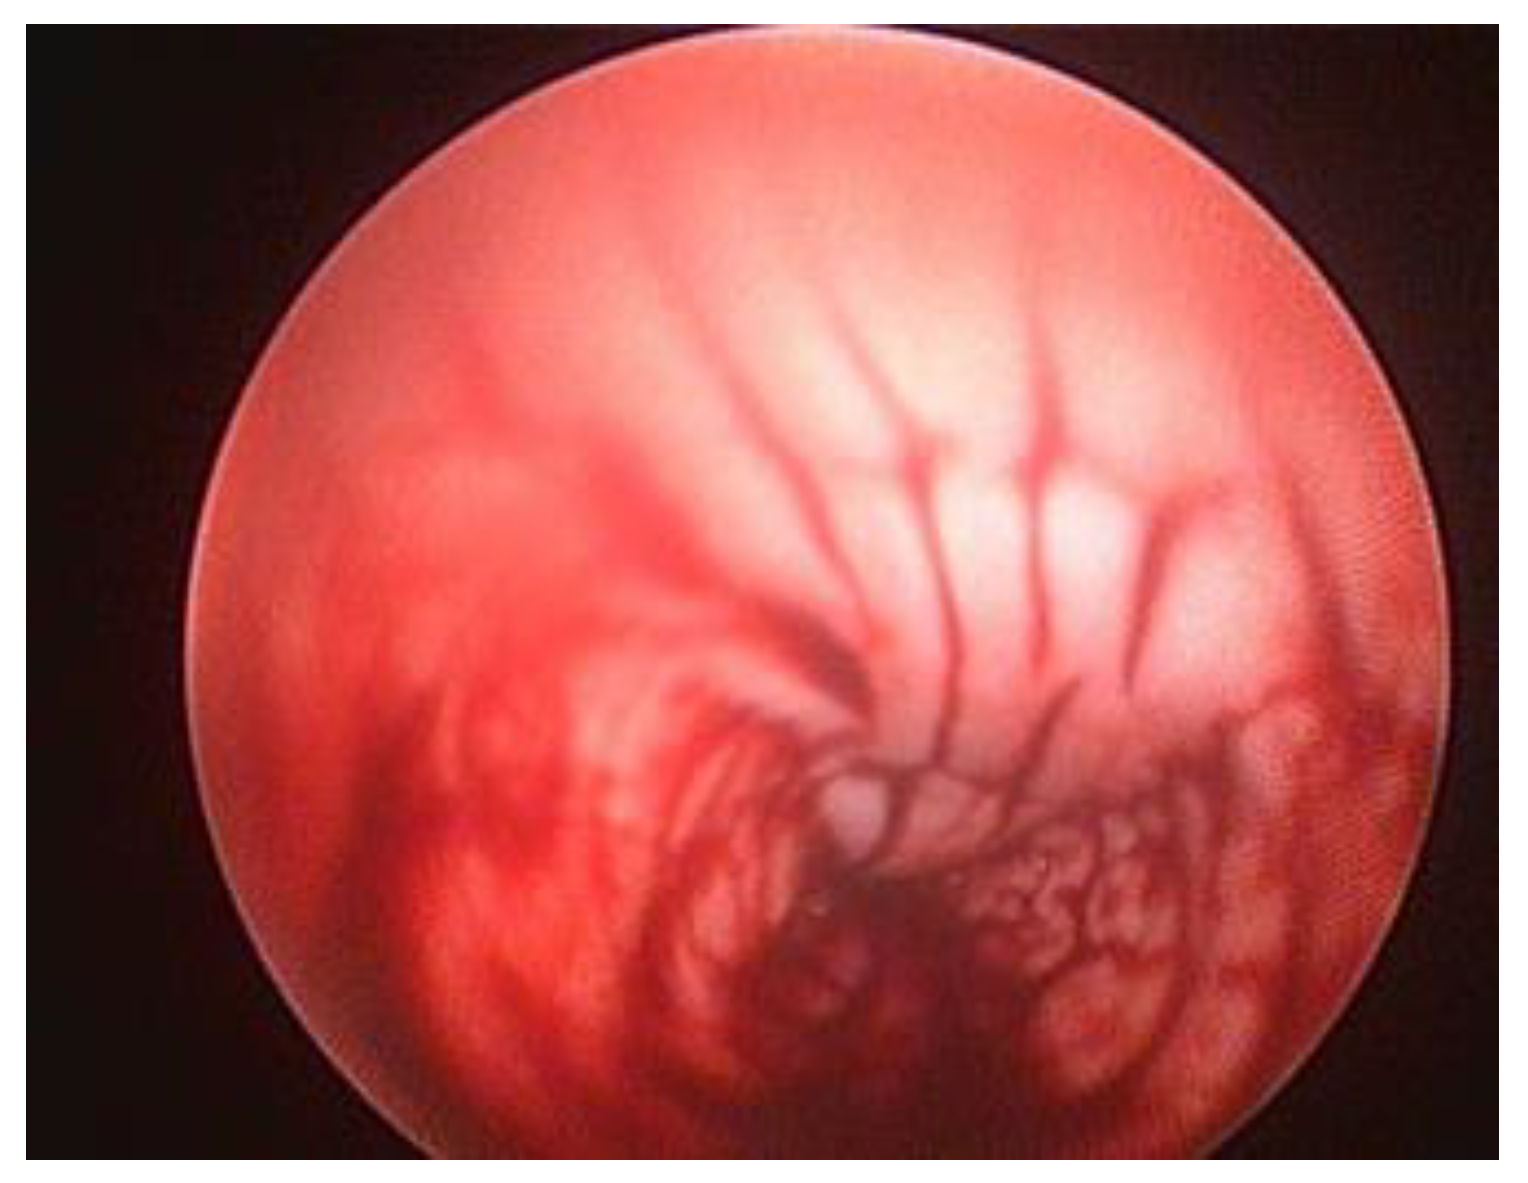

During urethrocystoscopy, attention should be directed to the appearance of the mucous membrane, its colour and surface characteristics, and the presence of erosion, lesions, and ulceration should be evaluated, Figure 4 [4]. Before inserting the endoscope into the urinary tract, the area of the external urethral orifice should be examined. Inflammation and neoplasms are the most frequent abnormalities observed in this region.

Figure 4. Endoscopic view of multiple extensive lesions in a mix-breed female dog at 7 days after unwanted breeding.